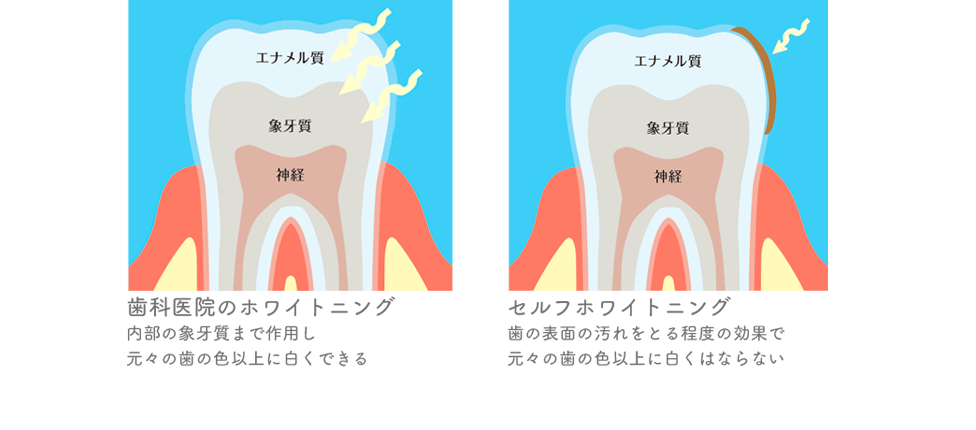

歯科医院では歯科専売の漂白剤(過酸化水素)を使用しており、歯の内部の象牙質まで作用して着色成分・黄ばみを分解し、白くします。

よって、元々の歯の色以上に白くすることができます。

*セルフホワイトニングで使用している薬剤は医薬品ではないため、歯の表面の汚れをとる作用しかなく、歯の内部の黄ばみを白くする効果はありません。よって、元々の歯の色以上に白くできませんのでご注意ください。

セルフホワイトニングとの違い